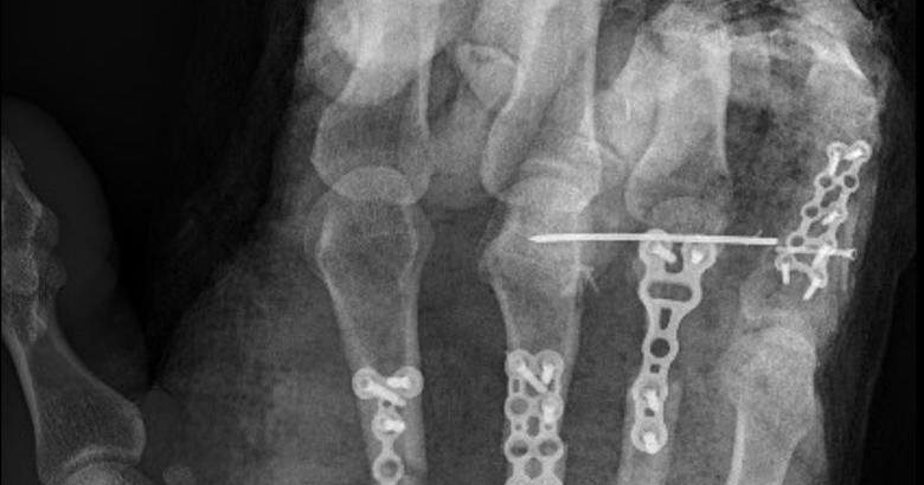

Pictured: X-ray of hand injury.

Dr Hadj said his patients often require extensive and complex reconstructive surgery, as well as one to two years of rehabilitation.

“Despite the significant advances in reconstructive repair, these patients will always have a degree of major impairment, so prevention is the best remedy,” he said.